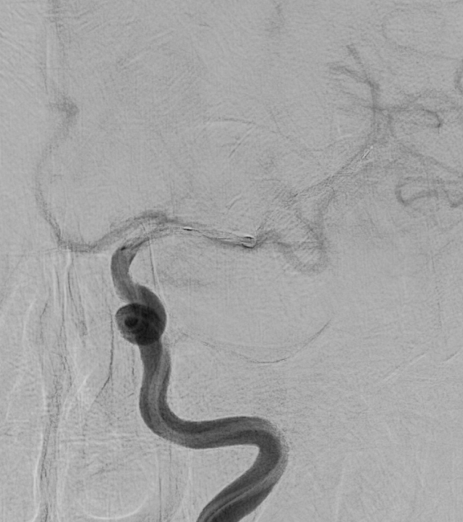

脳動脈瘤

【脳動脈瘤】

クリッピング後

【クリッピング後】

コイル塞栓術後

【コイル塞栓術後】

治療の方法は、開頭して動脈瘤にクリップをかけるクリッピングという方法と、コイル塞栓術といって頭を開けないでカテーテルで治療する方法があります。どちらの手段にも有利な点と不利な点があり、当院では動脈瘤の場所、形状、患者さんの状態などに応じて両者を使い分けています。